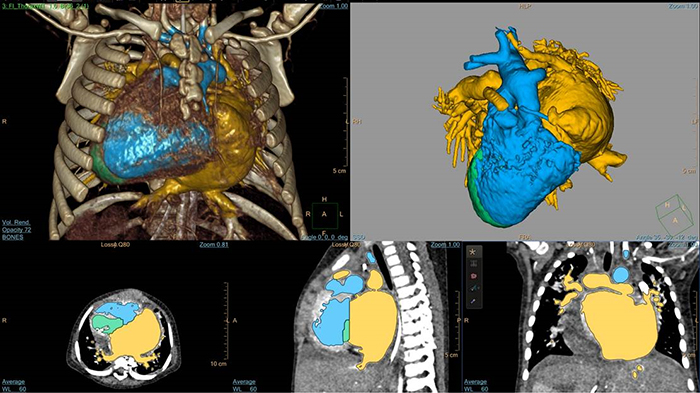

Cardiac TrueVue photorealistic rendering with MultiVue image alignment

3D modeling with IntelliSpace Portal